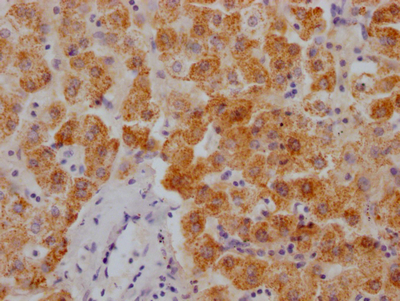

The image on the left is immunohistochemistry of paraffin-embedded Human brain tissue using CSB-PA297945(KRT13 Antibody) at dilution 1/35, on the right is treated with fusion protein. (Original magnification: ×200)

The image on the left is immunohistochemistry of paraffin-embedded Human cervical cancer tissue using CSB-PA297945(KRT13 Antibody) at dilution 1/35, on the right is treated with fusion protein. (Original magnification: ×200)